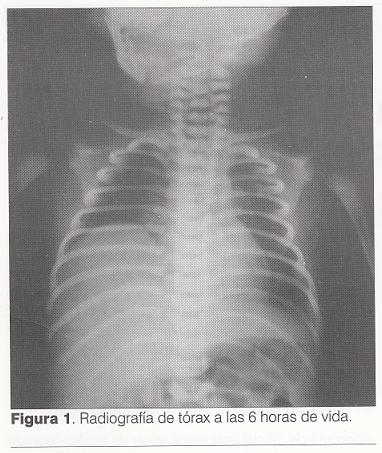

A las 6 horas de vida se obtuvo radiografía de tórax (figura 1) que evidenció elevación del hemidiafragma derecho, sin imágenes hidroaéreas intratorácicas anormales, ni desviación mediastinal, con transparencia pulmonar y silueta cardíaca normales. A las 18 horas de vida retrocedió el síndrome de dificultad respiratoria y se interrumpió la oxígenoterapia.